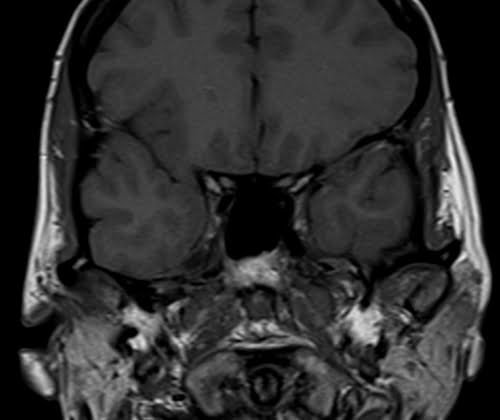

Brain epilipsy protocol mri coronal T1 images